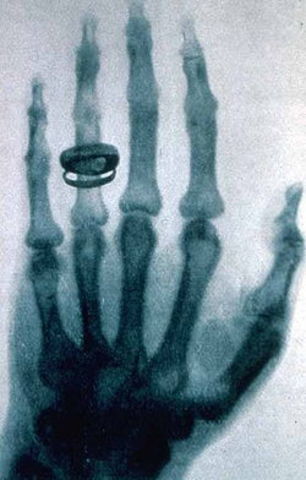

Los rayos X

El físico alemán Wilhelm Conrad Röntgen descubrió los rayos X en 1895, mientras experimentaba con los tubos de Hittorff-Crookes y la bobina de Ruhmkorff para investigar la fluorescencia violeta que producían los rayos catódicos. Tras cubrir el tubo con un cartón negro para eliminar la luz visible, observó un débil resplandor amarillo-verdoso proveniente de una pantalla con una capa de platino-cianuro de bario, que desaparecía al apagar el tubo.